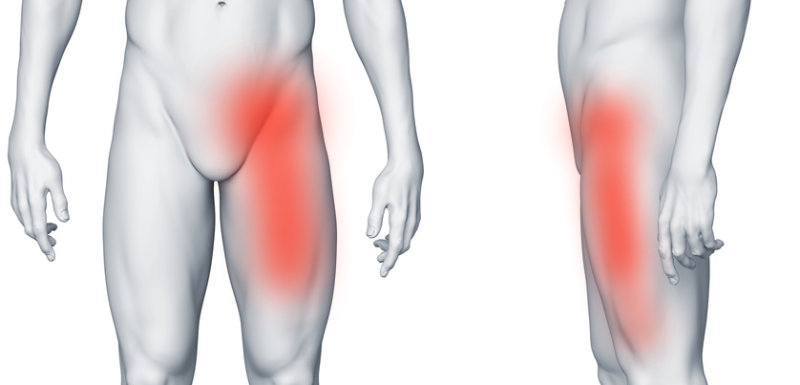

Przyczepy i mięśnie

Pachwina jest miejscem przyczepu wielu mięśni i więzadeł. Ich nadmierne przeciążenie może prowadzić do ich uszkodzenia. Ból w lewej pachwinie promieniujący na nogę często pojawia się u sportowców i jest wynikiem uszkodzenia mięśni (zwłaszcza przywodzicieli), bądź przyczepiających się do kości ścięgien i więzadeł.

Ból w lewej pachwinie promieniujący na nogę, zwłaszcza do przedniej części uda i kolana, może być objawem chorób stawu biodrowego, najczęściej jego zwyrodnienia, czyli koksartrozy. Dolegliwości często pojawiają się również w pośladku i biodrze oraz nasilają się podczas chodzenia.

Typową przyczyną zarówno rwy udowej jak i kulszowej jest dyskopatia lędźwiowa i ucisk na nerw rdzeniowy w kręgosłupie. Ucisk ten powoduje ból pośladka lub/i ból kręgosłupa lędźwiowego, który promieniuje do uda, podudzia i stopy. Ból w lewej pachwinie promieniujący do nogi jest bardziej charakterystyczny dla rwy udowej, jednak rwa kulszowa może również powodować dolegliwości w pachwinie.